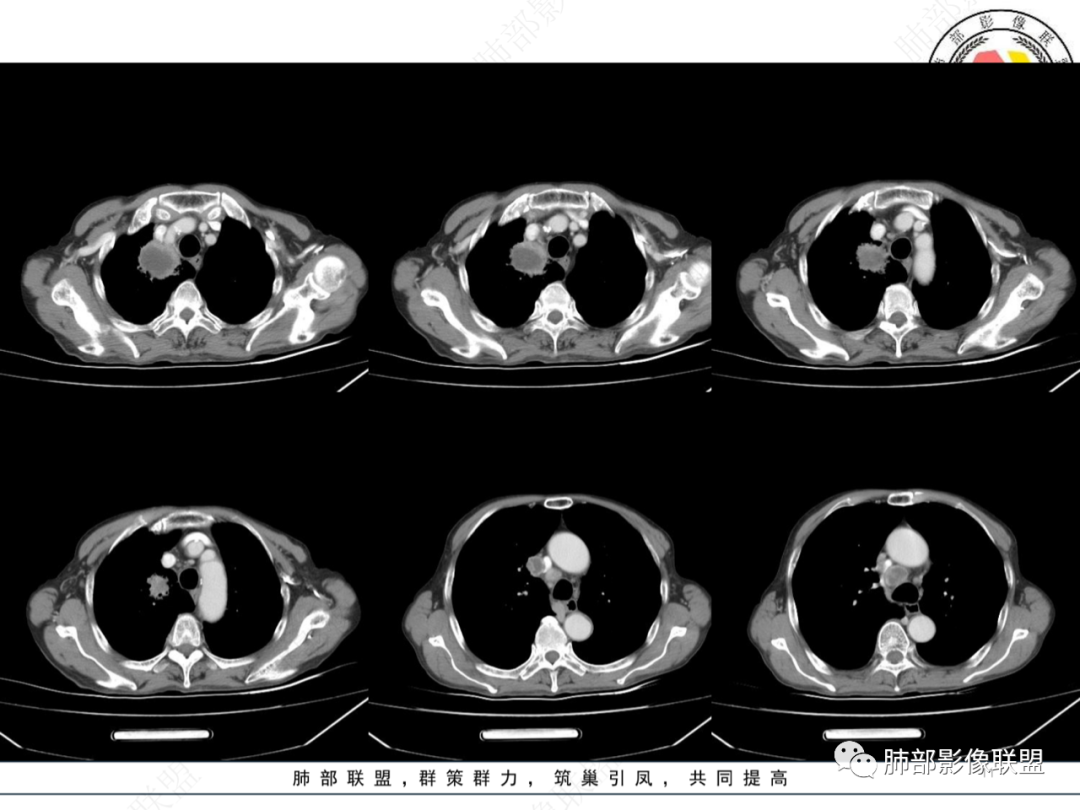

1月后,发热再次入院

这些新发的

合并有胸水

出现液气平面

治疗一周后复查

周围干净了,液平小了

壁似乎均匀了

治疗两周,病灶内气体没了

就目测看内壁还是清楚的

感染了:腔内就出现液气平面,附近大片高密度影

治疗后,腔内含气病灶少了

说明支气管通畅——狭窄——堵塞

我怀疑是不是堵塞口通了,腔内的坏死物播散到附近肺组织

抗炎后转后,支气管又收缩,堵了

患者有高血压、脑梗死、肾结石病史,因左胸痛不适入院,伴高热,血常规示白细胞、中性粒细胞高。胸部CT示右肺上叶肿块影,边缘模糊影,内可见低密度坏死,边界清楚,一月后出现气液平面,周围渗出,治疗2周复查液平及周围炎症吸收,肿块未见明显吸收。